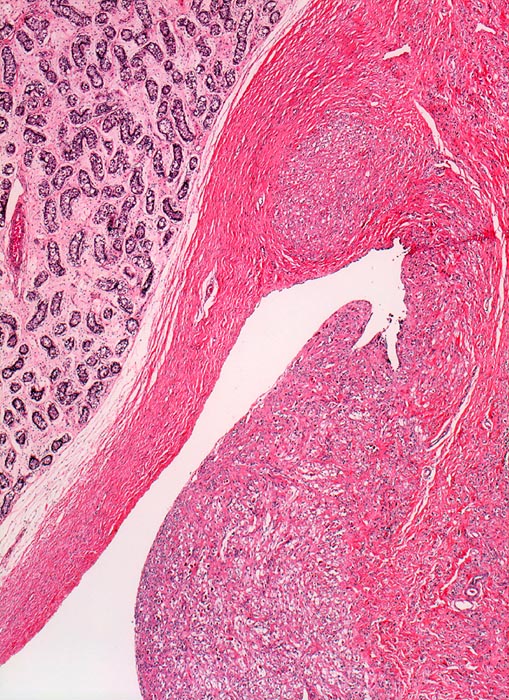

embryonales Rhabdomyosarkom des Samenstrangs

Funiculus spermaticus

Links im Bild der unreife Hoden eines präpubertären Knaben. Der anhaftende Samenstrang zeigt eine tumoröse Verdickung. Bereits in der Übersicht sind innerhalb des Tumors einzelne grosse Tumorzellen sichtbar, die in einem artefiziellen Spaltraum liegen.

Immunhistochemischer Nachweis von Myoglobin und Aktin in den Tumorzellen.

Rasch wachsender einseitiger Hodentumor. Hydrocele.

Rhabdomyosarkome treten praktisch nur bei Kindern auf. Das embryonale Rhabdomyosarkom hat eine intermediäre Prognose. Die meisten paratestikulären Rhabdomyosarkome sind vom embryonalen Typ.